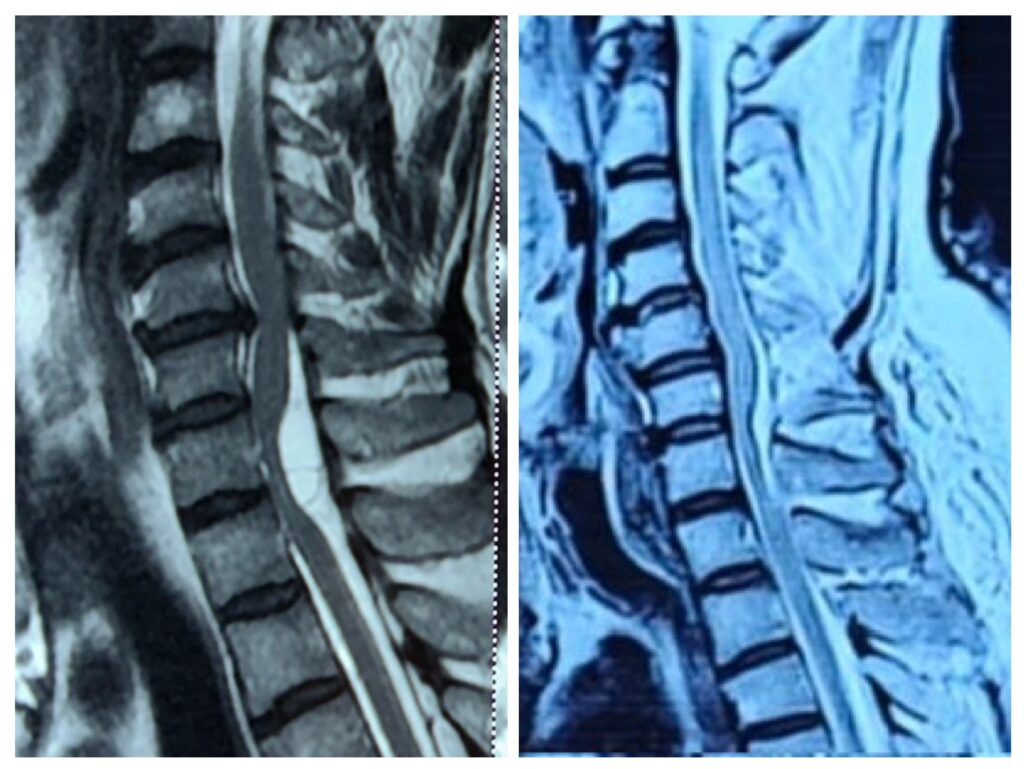

• MRI scan: The most important test to detect spinal cord tumors clearly

These tests help determine the tumor’s size, type, and exact location.

Cases treated by Spine Specialist Dr. Gaurav Sandeep Gupta